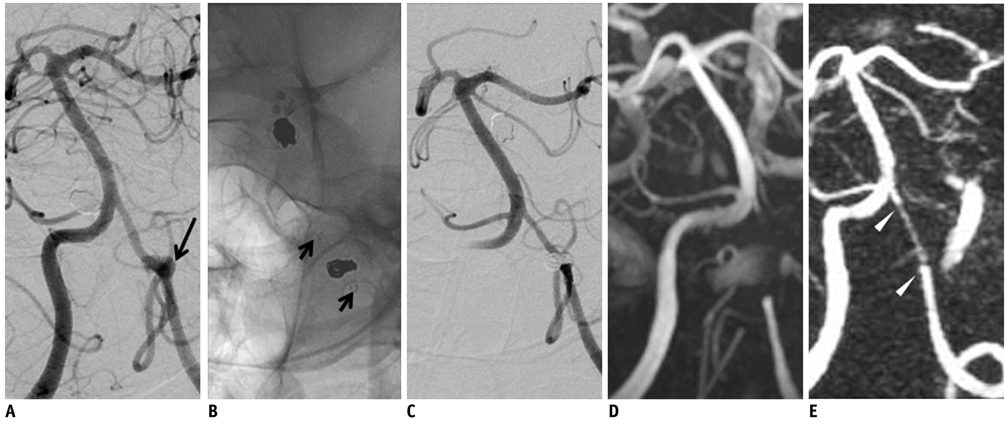

To evaluate the usefulness of time-resolved contrast enhanced magnetic resonance angiography (4D MRA) after stent-assisted coil embolization by comparing it with time of flight (TOF)-MRA.

TOF-MRA and 4D MRA were obtained by 3T MRI in 26 patients treated with stent-assisted coil embolization (Enterprise:Neuroform = 7:19). The qualities of the MRA were rated on a graded scale of 0 to 4. We classified completeness of endovascular treatment into three categories. The degree of quality of visualization of the stented artery was compared between TOF and 4D MRA by the Wilcoxon signed rank test. We used the Mann-Whitney U test for comparing the quality of the visualization of the stented artery according to the stent type in each MRA method.

RESULTS

The quality in terms of the visualization of the stented arteries in 4D MRA was significantly superior to that in 3D TOF-MRA, regardless of type of the stent (p < 0.001). The quality of the arteries which were stented with Neuroform was superior to that of the arteries stented with Enterprise in 3D TOF (p < 0.001) and 4D MRA (p = 0.008), respectively.

4D MRA provides a higher quality view of the stented parent arteries when compared with TOF.